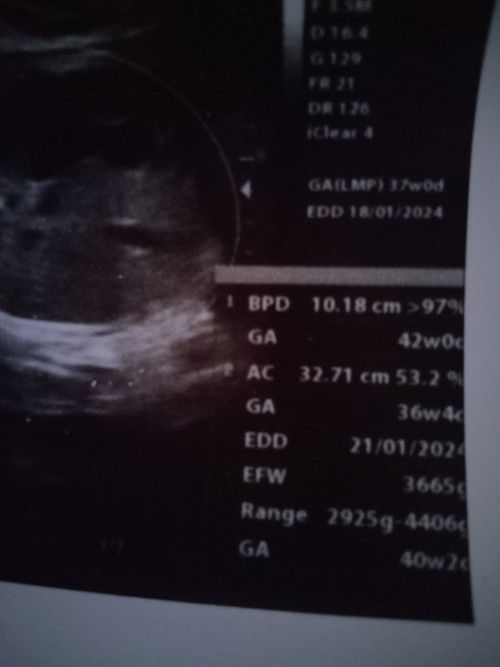

Menanyakan hasil usg

Bunda bunda atau disini ada bidan yang bisa baca hasil usg,,,, Apakah hasil usg saya bagus?dan apakah bbj 3665gr di usia kehamilan 37 week tidak kebesaran?